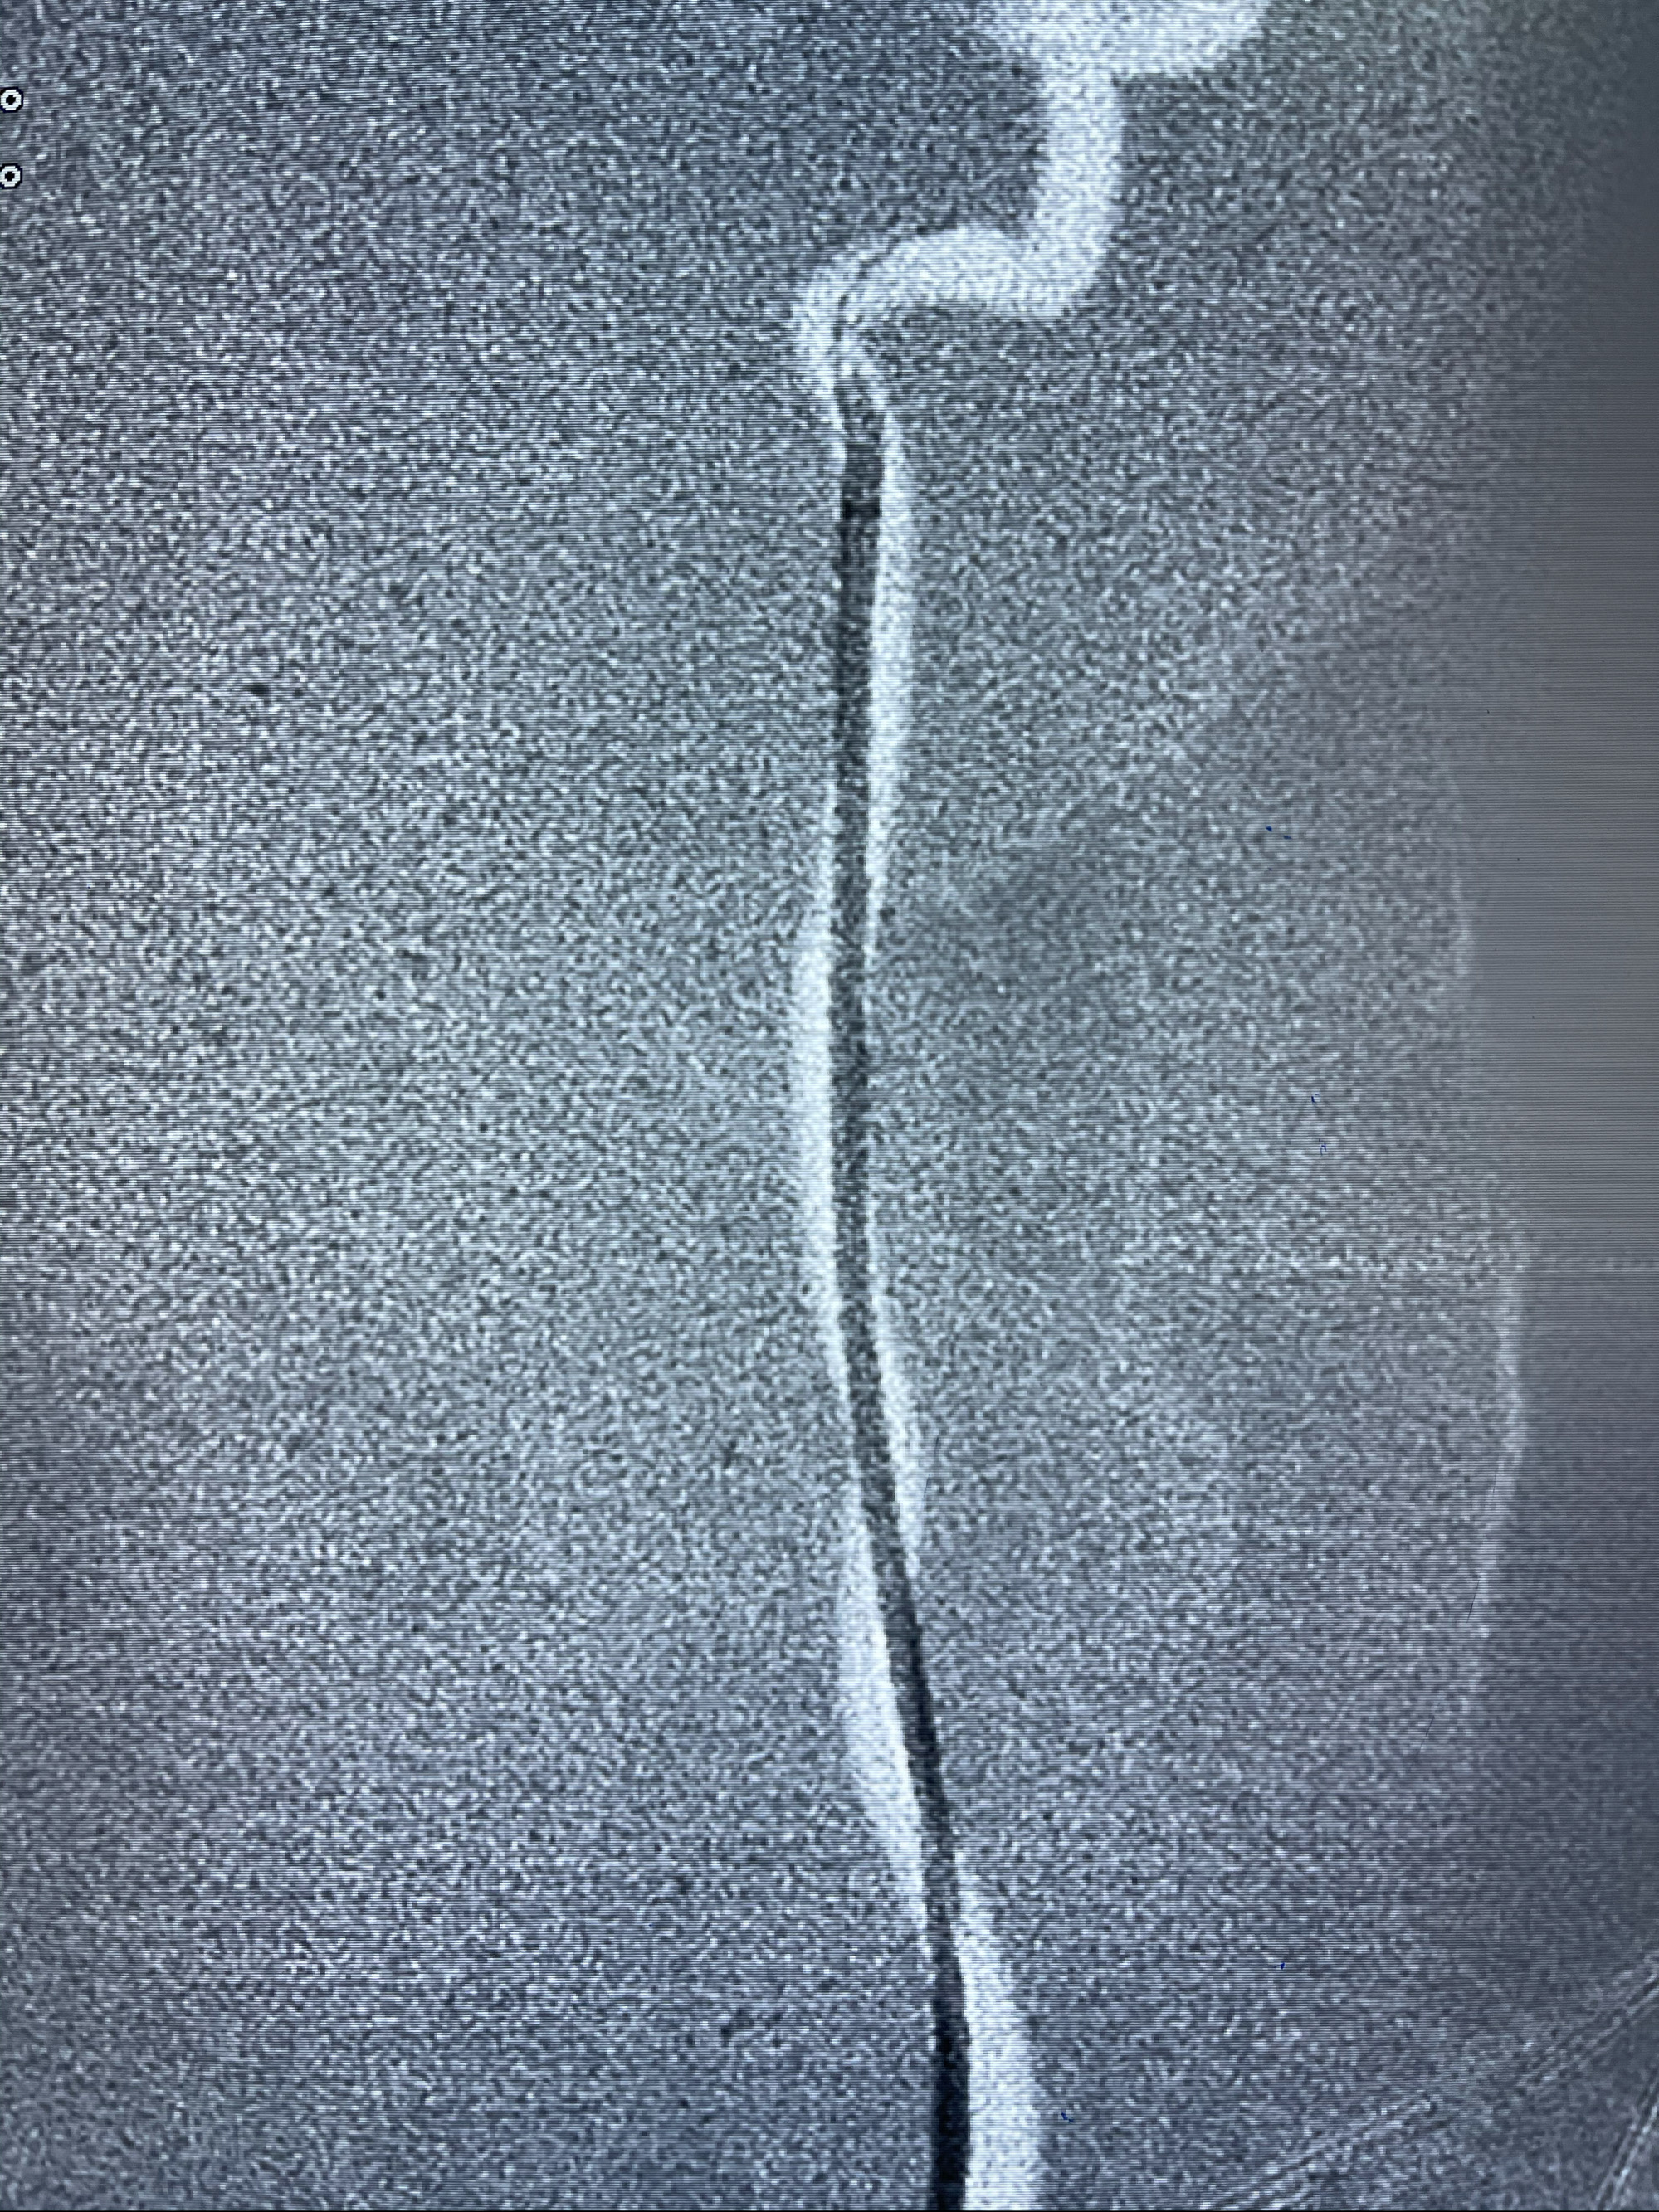

支架到位

支架释放,透视下